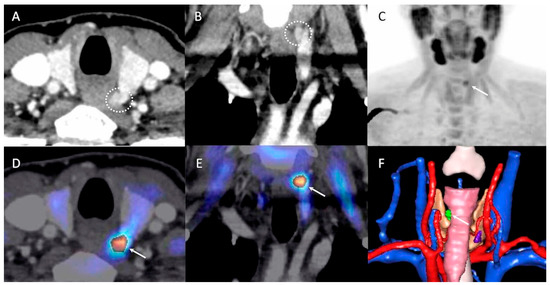

- Piccardo, A.; Trimboli, P.; Rutigliani, M.; Puntoni, M.; Foppiani, L.; Bacigalupo, L.; Crescenzi, A.; Bottoni, G.; Treglia, G.; Paparo, F.; et al. Additional value of integrated 18F-choline PET/4D contrast-enhanced CT in the localization of hyperfunctioning parathyroid glands and correlation with molecular profile. Eur. J. Nucl. Med. Mol. Imaging 2019, 46, 766–775. [Google Scholar] [CrossRef]

- D’Agostino, J.; Wall, J.; Soler, L.; Vix, M.; Duh, Q.Y.; Marescaux, J. Virtual neck exploration for parathyroid adenomas: A first step toward minimally invasive image-guided surgery. JAMA Surg. 2013, 148, 232–238. [Google Scholar] [CrossRef]

- D’Agostino, J.; Diana, M.; Vix, M.; Nicolau, S.; Soler, L.; Bourhala, K.; Hassler, S.; Wu, H.S.; Marescaux, J. Three-dimensional metabolic and radiologic gathered evaluation using VR-RENDER fusion: A novel tool to enhance accuracy in the localization of parathyroid adenomas. World J. Surg. 2013, 37, 1618–1625. [Google Scholar] [CrossRef] [PubMed]